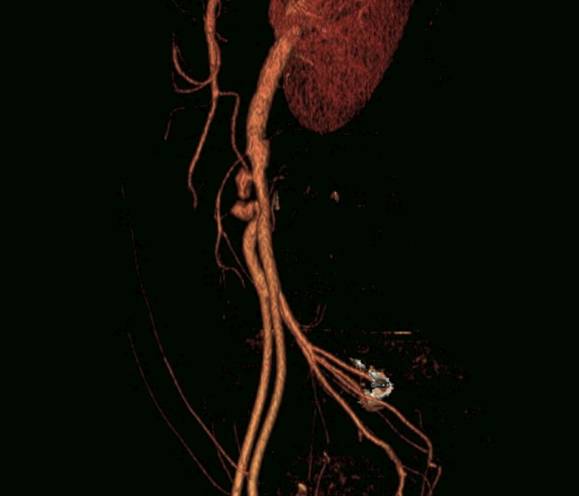

Pain and numbness of right lower limb (71 / M)

Ji Won Lee, Department of Radiology, Pusan National University Hospital

HIT : 23